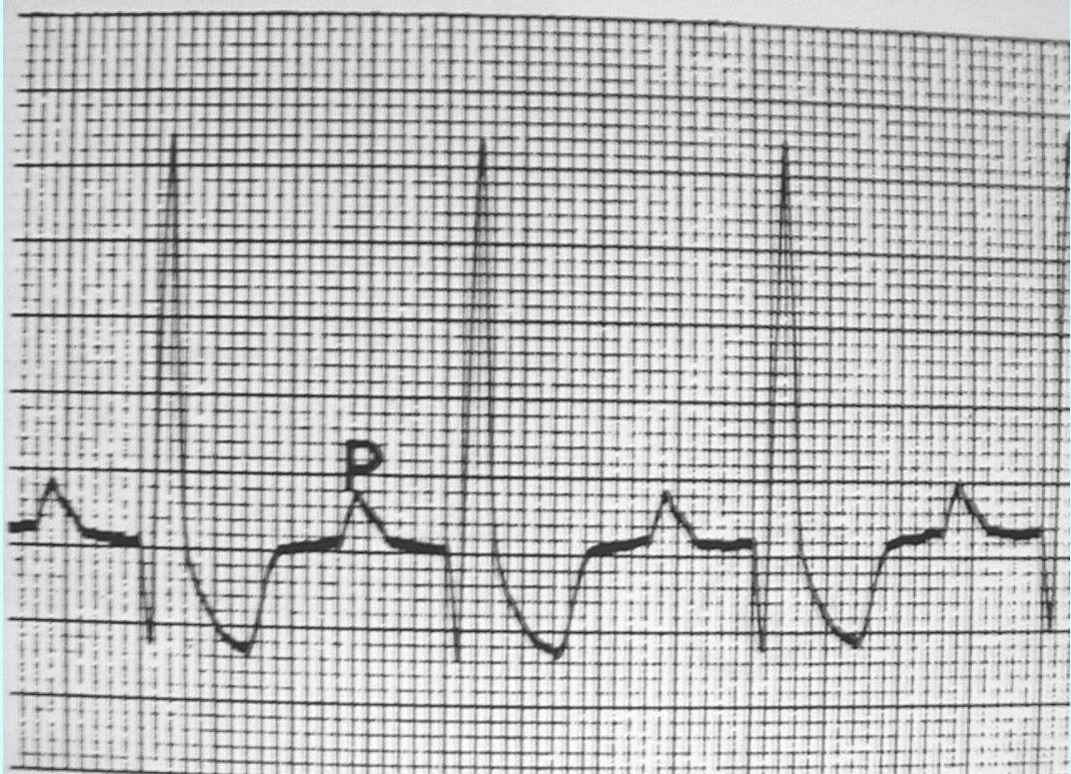

what are the different parts of an ECG and what do they represent

SA node fires sending signal to atria to contract, that gives the P wave

then the signal continues through AV node, bundle of His, bundle branches & Purkinje fiber and the QRS complex starts representing ventricular depolarization (which should in turn lead to ventricular contraction)

then when the ventricles repolarize the T wave appears

and the cycle starts again

Name this part of ECG

P wave

Name this part of ECG segment

R-R interval

R wave

ST segment

S wave

QRS wave